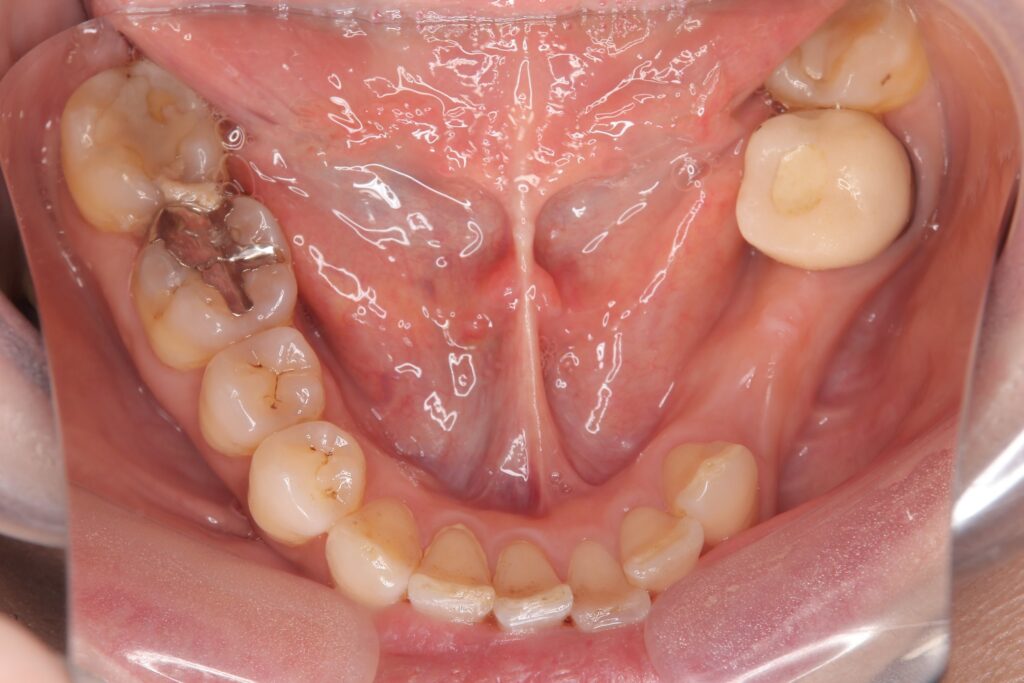

インプラント治療後の写真とレントゲン写真

インプラント治療により、自然な見た目で、ご自身で取り外す必要がなく快適に過ごすことができるようになったと考える。また、インプラント治療により人工歯根が噛む力を支える柱となり、その他の歯に過剰な負担がかかるリスクを軽減できたと考える。

費用【税込】:約100万

内容:下顎左側第一小臼歯、第二小臼歯に対するインプラント治療

期間:6ヶ月(抜歯を含む)